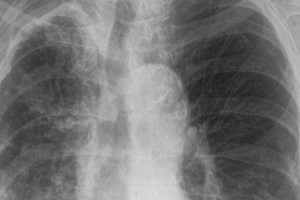

Tuberkuloza je bolest koja se danas dosta lako dijagnosticira. Važno je uzeti dobru anamnezu i obaviti pregled pacijenta, načiniti laboratorijske nalaze i RTG...

Iako izlječiva, tuberkuloza i danas najsmrtonosnija zarazna bolest – U prošloj godini, prema podacima Federalnog registra za tuberkulozu, prijavljeno je...